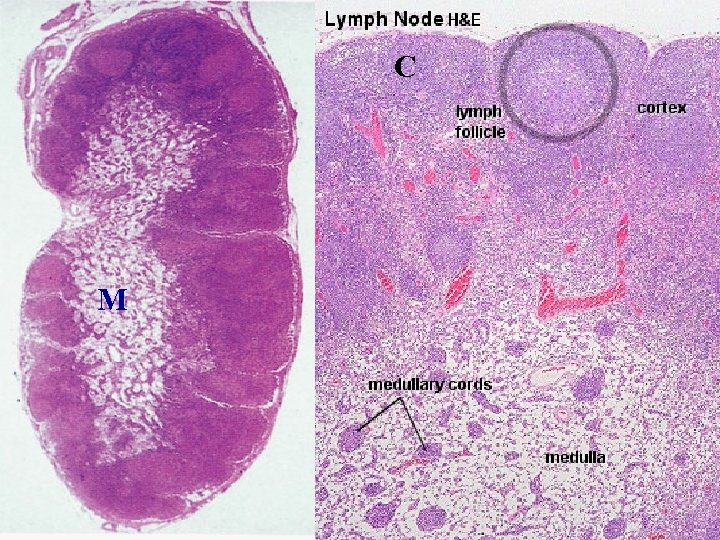

Lymph Node • • • Capsulated Afferent lymphatics “subcapsular sinus” Hilum – blood vessels, efferent lymphatic Cortex and medulla Cortex – Lymphatic nodules, germinal centres – “Paracortex” T-dependent zone • Medulla – Medullary cords and sinusoids M C

LYMPH NODES These are the smallest but most numerous encapsulated lymphoid organs. Scattered in groups along lymphatic vessels , they act as in-line filters of the lymph, removing antigens and cellular debris and adding Igs. Lymph nodes are bean-shaped structures with convex and concave surfaces. The parenchyma consists of a peripheral cortex, adjacent to the convex surface, and a central medulla lying near the depression (hilum) in the concave surface. The connective tissue capsule gives off trabeculae that penetrate between the cortical nodules and subdivide the cortex. Cortex. The cortex is dark-staining owing to the presence of tightly packed lymphocytes. These are suspended in a reticular connective tissue network and arranged as a layer of typical secondary lymphoid nodules (containing primarily B lymphocytes) with germinal centers. The cortex also contains reticular cells, antigen-presenting follicular dendritic cells, macrophages, a few plasma cells, and some helper T cells.

Medulla. Lighter staining than the cortex, the medulla is composed of cords of lymphoid tissue (medullary cords) separated by medullary sinuses. The lymphocytes are mainly small, less numerous than in the cortex. The cords are also rich in reticular cells and fibers and contain many plasma cells that have migrated from the cortex. Paracortical zone. This is the T-dependent region, lying between the cortical lymphoid nodules and the medulla. It contains mainly T lymphocytes suspended in a reticular connective tissue. B lymphocytes, plasma cells, macrophages, and antigen-presenting interdigitating dendritic cells may also be present. Lymphatic vessels. Sinuses (subcapsular, peritrabecular, medullary). Functions: 1. Filtration of lymph 2. Lymphocyte production (lymphopoiesis). 3. Immunoglobulin production.